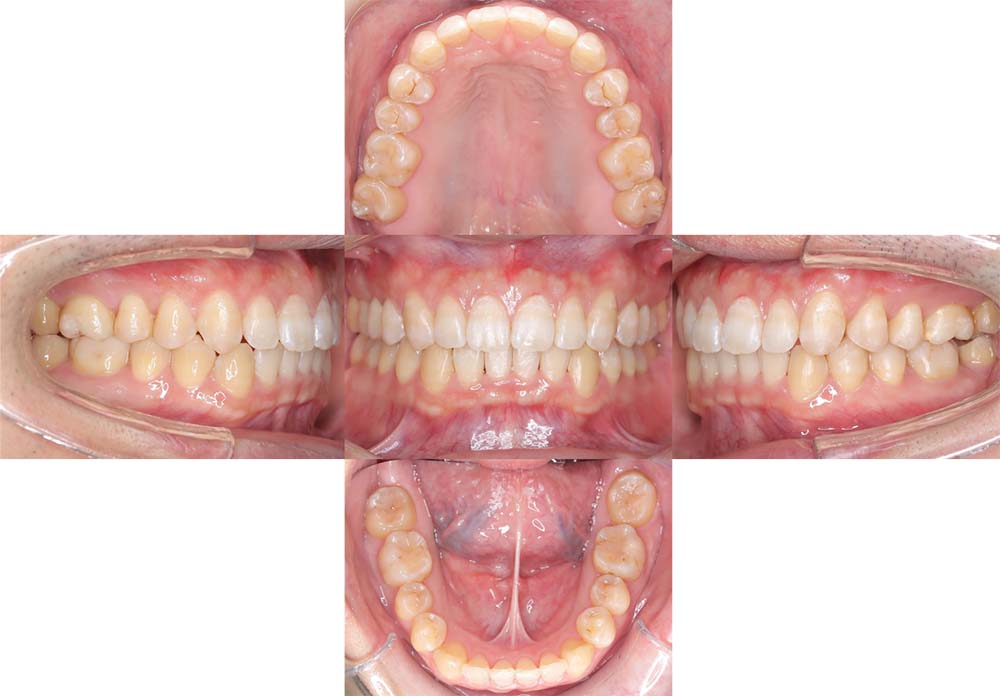

症例03

| 主訴 | 歯並びがガタガタしている。 |

| 診断名あるいは主な症状 | 過蓋咬合、叢生 |

| 年齢/性別 | 26歳・女性 |

| 矯正ステージ | 大人の矯正治療 |

| 治療方法 |

ワイヤー矯正 歯科矯正用アンカースクリュー(3本) |

| 抜歯部位/抜歯有無 | 抜歯 |

| 治療内容 | 上下顎の奥歯を後方に移動後、ガタガタの改善と上下顎前歯を後退させた。 |

| 費用 |

90万円程度(2025.10時点の料金となります。) ※矯正基本料金、アンカースクリュー、審美ブラケットを含む |

| 治療期間 | 2年8ヶ月 |

| 主なリスク・副作用 | 痛み、歯根吸収、歯肉退縮、虫歯、後戻り |